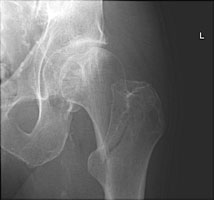

- Click on the image for a larger versionDAP radiograph of the right hip. A third example of an intertrochanteric fracture.